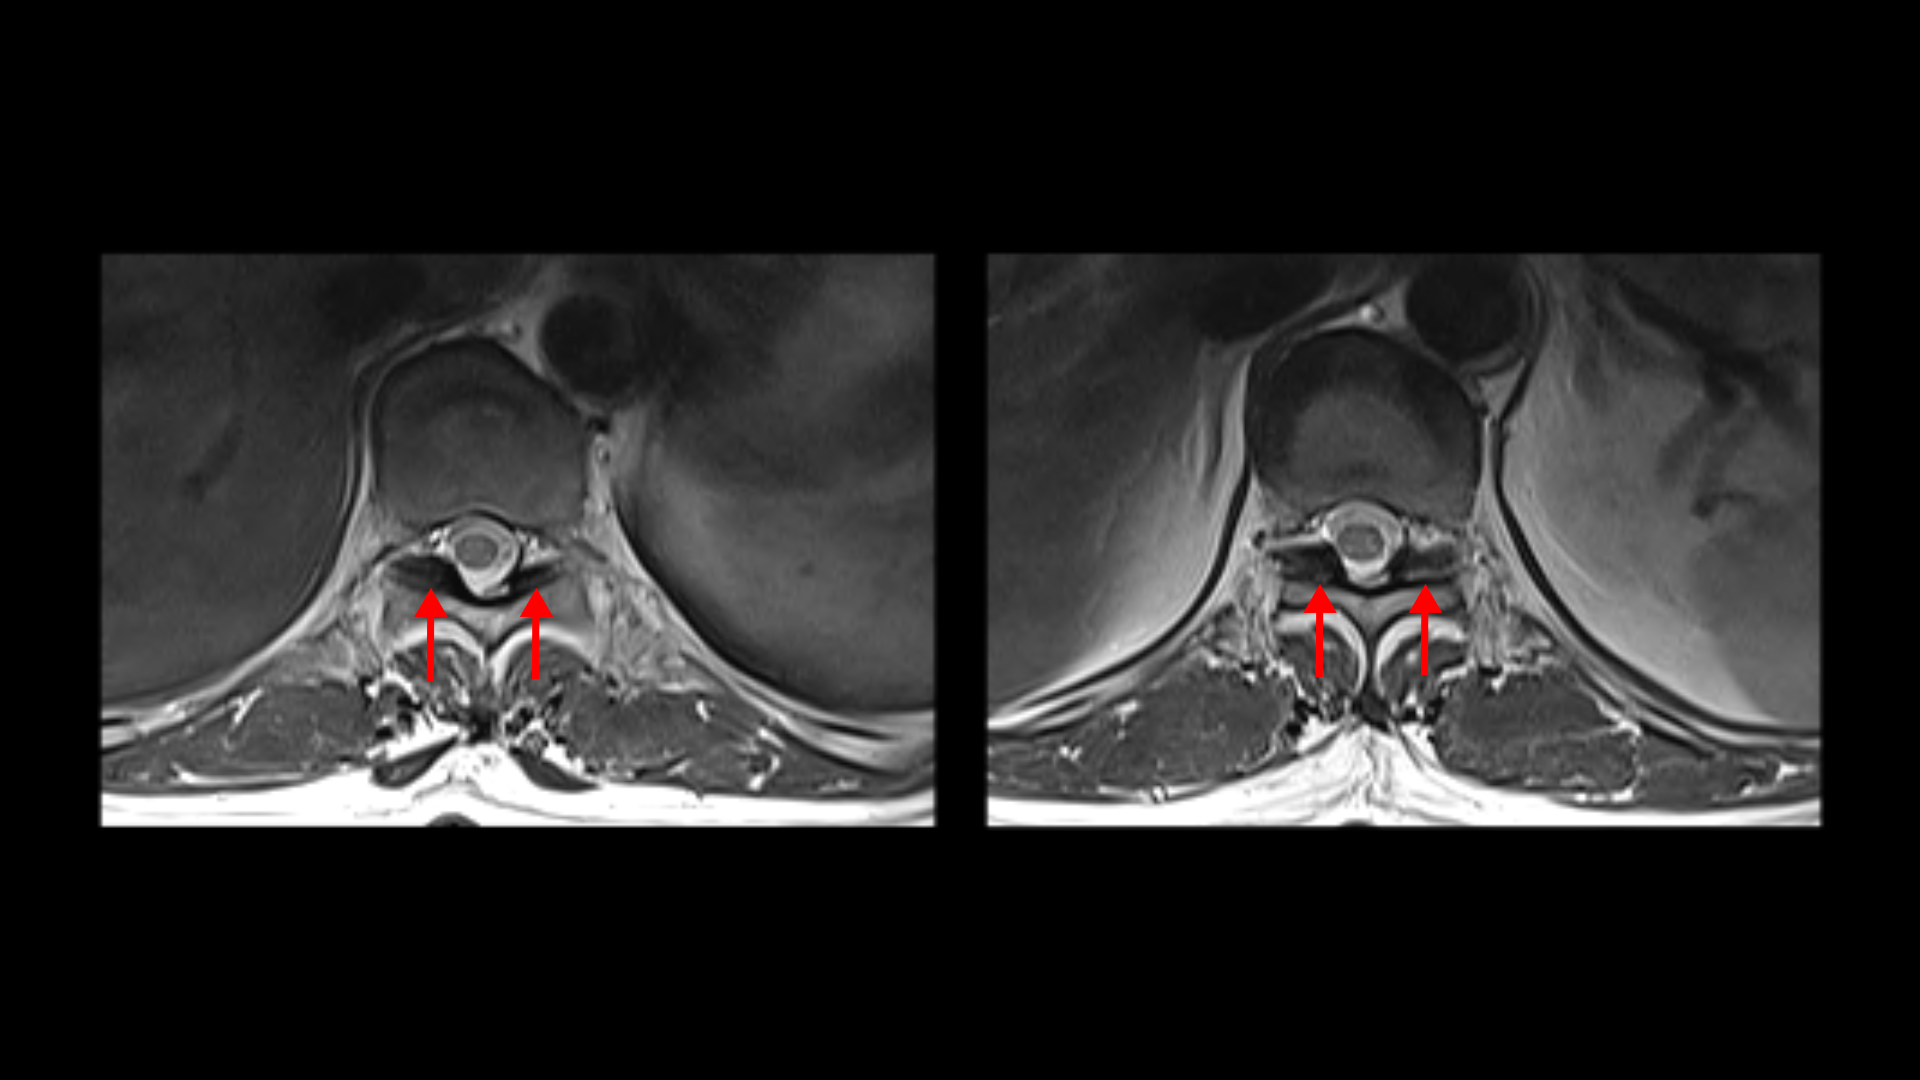

흉추 두 마디에서도 역시 황색인대의 골화 현상이 보입니다.

그리고 허리 4마디에 퇴행성 허리디스크가 있습니다.